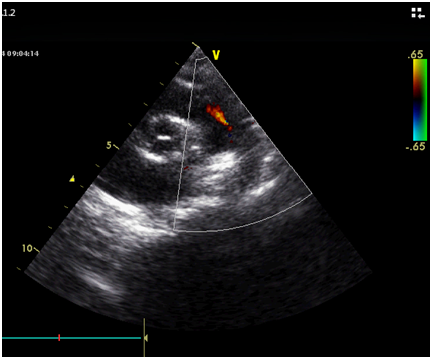

Echocardiography showed: PDA 4 mm with left to right shunt (Figure 2).

Figure 2 Short axis view Echocardiogram showed the size of the PDA.